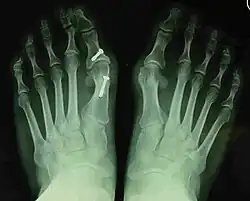

Before_syndesmosis_surgery

Fig. 4a: Before surgery

2_years_after_syndesmosis_surgery

Fig. 4b: 2 years after surgery

Syndesmosis procedure addresses specifically the two fundamental problems of metatarsus primus varus deformity that gives rise to the bunion deformity. They are leaning and instability of the first metatarsal bone . Syndesmosis procedure uprights the leaning first metatarsal bone with strong binding sutures between it and the second metatarsal bone (Fig. 2) and then also stabilizes it uniquely by creating a fibrous connecting bridge between these two bones (Fig. 3, 4). First metatarsal bone can be readily realigned because by definition of the metatarsus primus varus deformity its first metatarsal is abnormally loose and mobile.